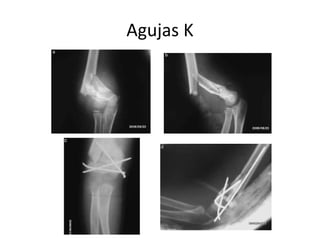

Agujas K

Fracturas no desplazadas o mínimamente

desplazadas con correcta congruencia articular